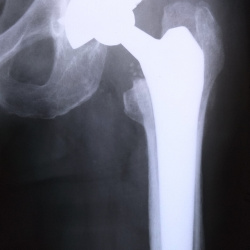

Мужчина 1978 г.р. в 2022г травма и операция. В мае 2025 повторная травма, перелом металлоконструкции и костей. В лечебном учреждении нашего города специализированную помощь оказывать не стали в связи...